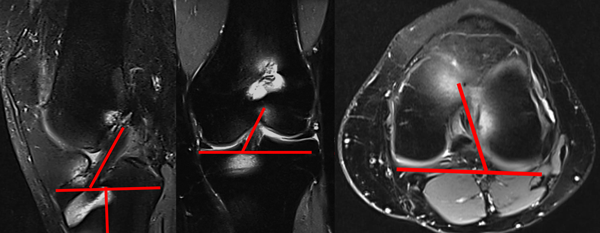

En las imágenes de RM, al neoligamento se lo evaluó en los tres planos (sagital, coronal y axial).

El ángulo de orientación en el plano sagital se midió trazando una línea que corresponde al eje longitudinal de la diáfisis tibial y una línea perpendicular a la altura de los platillos tibiales; posteriormente se trazó otra línea paralela a las fibras del LCA, según sus huellas de inserción, el ángulo agudo formado por estas dos últimas es el ángulo de inclinación resultante.

Para el ángulo de orientación en el plano coronal se trazó una línea entre el punto medio de la inserción distal y proximal de las fibras del LCA y otra línea paralela a la superficie de los platillos tibiales, el ángulo agudo resultante entre estas dos líneas es el que se registró.

En el ángulo de orientación en el plano axial se trazó una línea entre el punto medio de la inserción distal y proximal de las fibras del ligamento cruzado anterior y otra línea tangencial al aspecto posterior de los cóndilos femorales, el ángulo resultante entre estas dos corresponde al ángulo de inclinación (fig. 5).

Figura 5: Orientación del injerto en el plano sagital, coronal y axial.